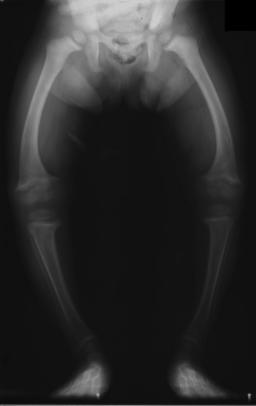

| X-ray of a two-year-old with rickets, with a marked bowing of the femurs and decreased bone density | |

تميل الأشعة السينية أو التصوير الشعاعي لمريض متقدم يعاني من الكساح إلى الظهور بطريقة كلاسيكية: الأرجل المنحنية (الانحناء الخارجي لعظم الساق الطويلة) والصدر المشوه. تحدث التغييرات في الجمجمة أيضًا مما يؤدي إلى ظهور "رأس مربع" مميز يُعرف باسم "caput quadratum".[15] تستمر هذه التشوهات في سن البلوغ إذا لم يتم علاجها تشمل العواقب طويلة المدى التقوس الدائم أو تشوه العظام الطويلة والظهر المنحني[16]

- يظهر التصوير الشعاعي عادة اتساع مناطق التكلس المؤقت للكراديس الثانوية للعظم غير المعدني. عادة ما تظهر التجلف ، والابلاء ، والتفلطح في الكراديس مع النمو وتحمل الوزن المستمر.[37] تُرى هذه التغييرات في الغالب في مواقع النمو السريع ، بما في ذلك عظم العضد القريب ، والزند البعيد ، وعظم الفخذ البعيدة وكل من الظنبوب الداني والبعيدة. لذلك ، يمكن إجراء مسح للهيكل العظمي للكساح باستخدام الصور الشعاعية الأمامية الخلفية للركبتين والمعصمين والكاحلين.[37]